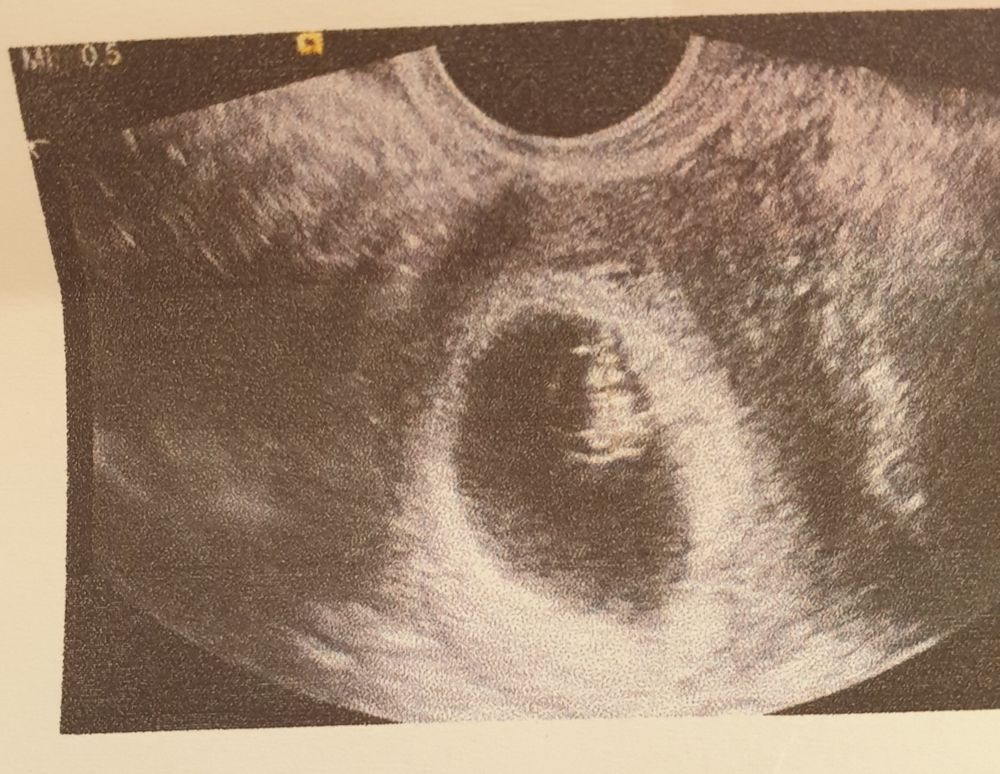

Метод рамзи . Давайте гадать

На девочку

Алена дзюба, по прикреплению на сроке 6-8 недель,если трансвагинально: то слева -мальчик,справа -девочка,если по животу( абдоминально) то наооброт

У меня совпало с обеими девчулями, ставлю на девочку 🥰

Зеркально если, то девочка

Девочка